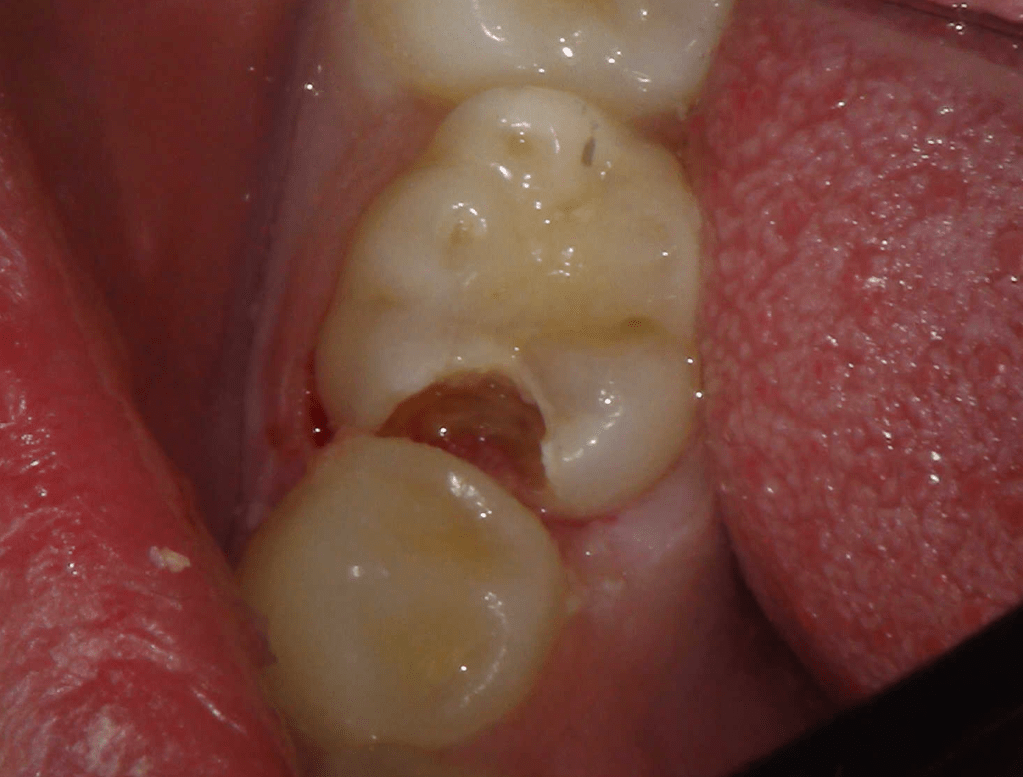

Reco pre-endo, molar inferior